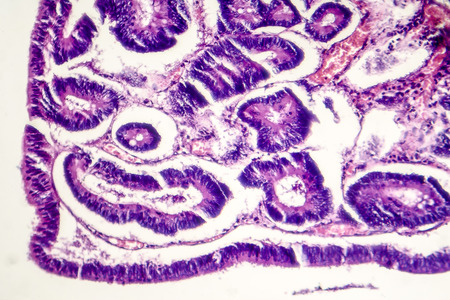

Small intestine with villi under the microscope 100x